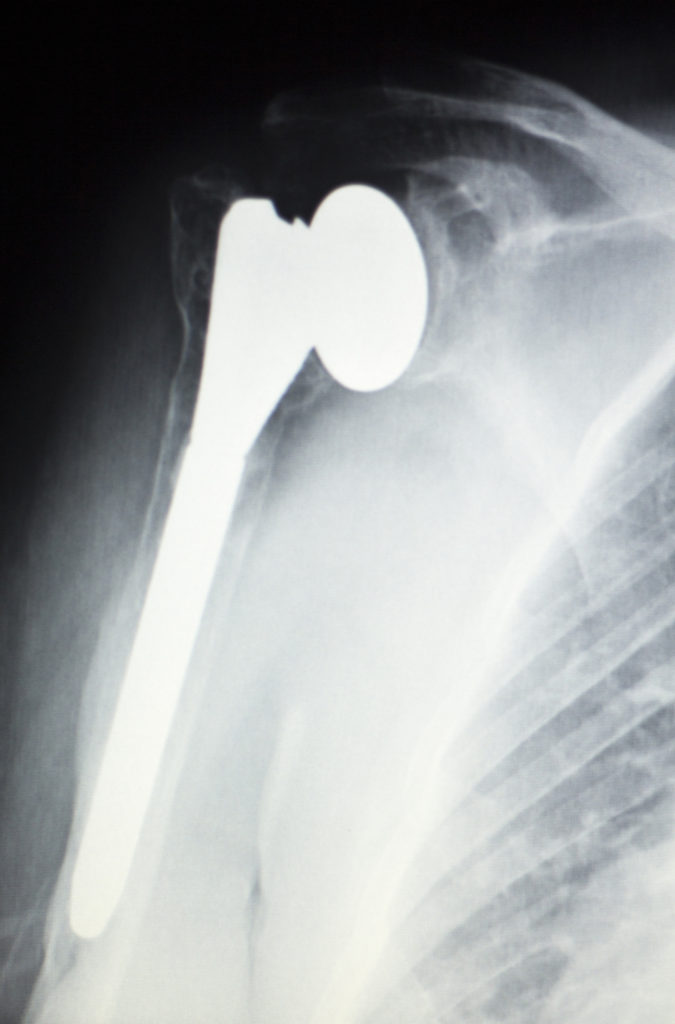

A traditional shoulder replacement procedure involves replacing the damaged part of the shoulder joint with prosthetics. Your orthopedic surgeon will surgically implant artificial parts for the ball-and-socket joint of the shoulder. This means replacing the “socket” area of the shoulder blade and/or the “ball” portion at the top of the upper arm. Once in place, the prosthetics should seamlessly mimic the natural movements of the shoulder. A special cement is used to make the synthetic components stick.

In a reverse procedure, the position of the “ball” and “socket” are reversed. Your surgeon will implant a prosthetic ball at the shoulder blade, and an artificial socket at the top of the upper arm.